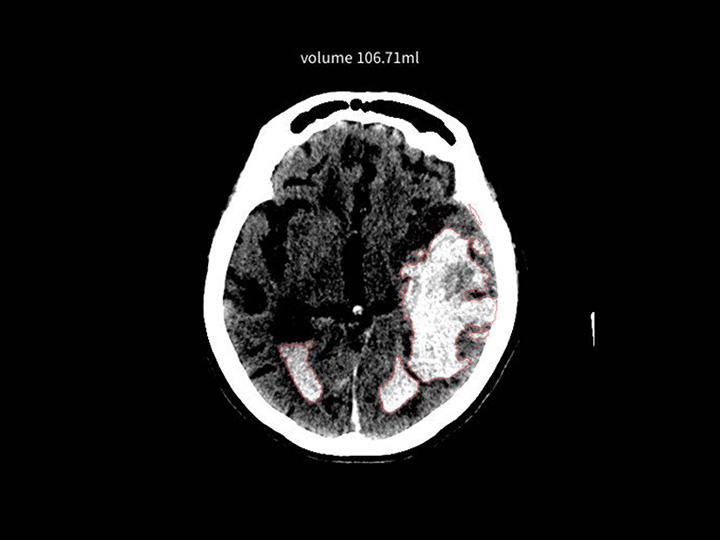

導入の相談はこちら頭部CT×高吸収/低吸収域

DoctorNET Heuron CTS

頭部非造影CT画像から、画像内の高吸収域または低吸収域を検出します

- 救急現場での読影補助として

- 頭部が専門ではない先生の補助として

- 販売名

- 頭部CT画像解析AIエンジン DoctorNet Heuron CTS

- 医療機器承認番号

- 307AGBZX00052000

- 一般的名称

- 汎用画像診断装置ワークステーション用プログラム

- クラス分類

- クラスII

- 承認年月日

- 令和7年10月2日

- 種別

- プログラム(01) 疾病診断用プログラム